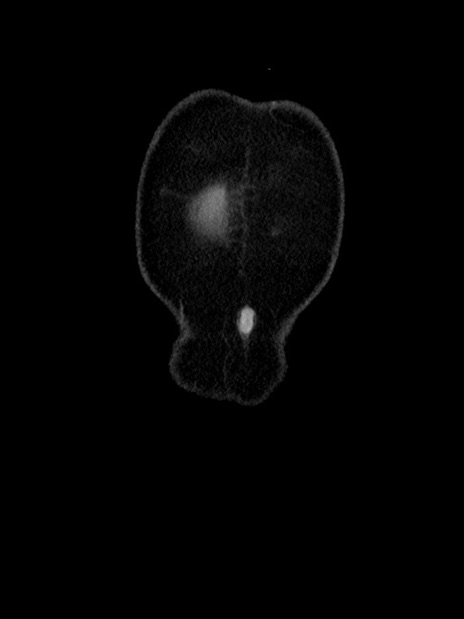

症例35(冠状断像)

【症例】70歳代 男性

【主訴】腹部膨満、嘔吐

【現病歴】昨日より腹部膨満感出現。本日増悪し、仙痛出現。嘔吐あり、受診。

【既往歴】糖尿病、胆摘後

【身体所見】BP 149/80mmHg、HR 74/min、BT 35.9℃、腹部:膨満、軟、圧痛なし。腸雑音減弱あり。上腹部正中切開瘢痕あり。

【データ】WBC 13500、CRP 1.72